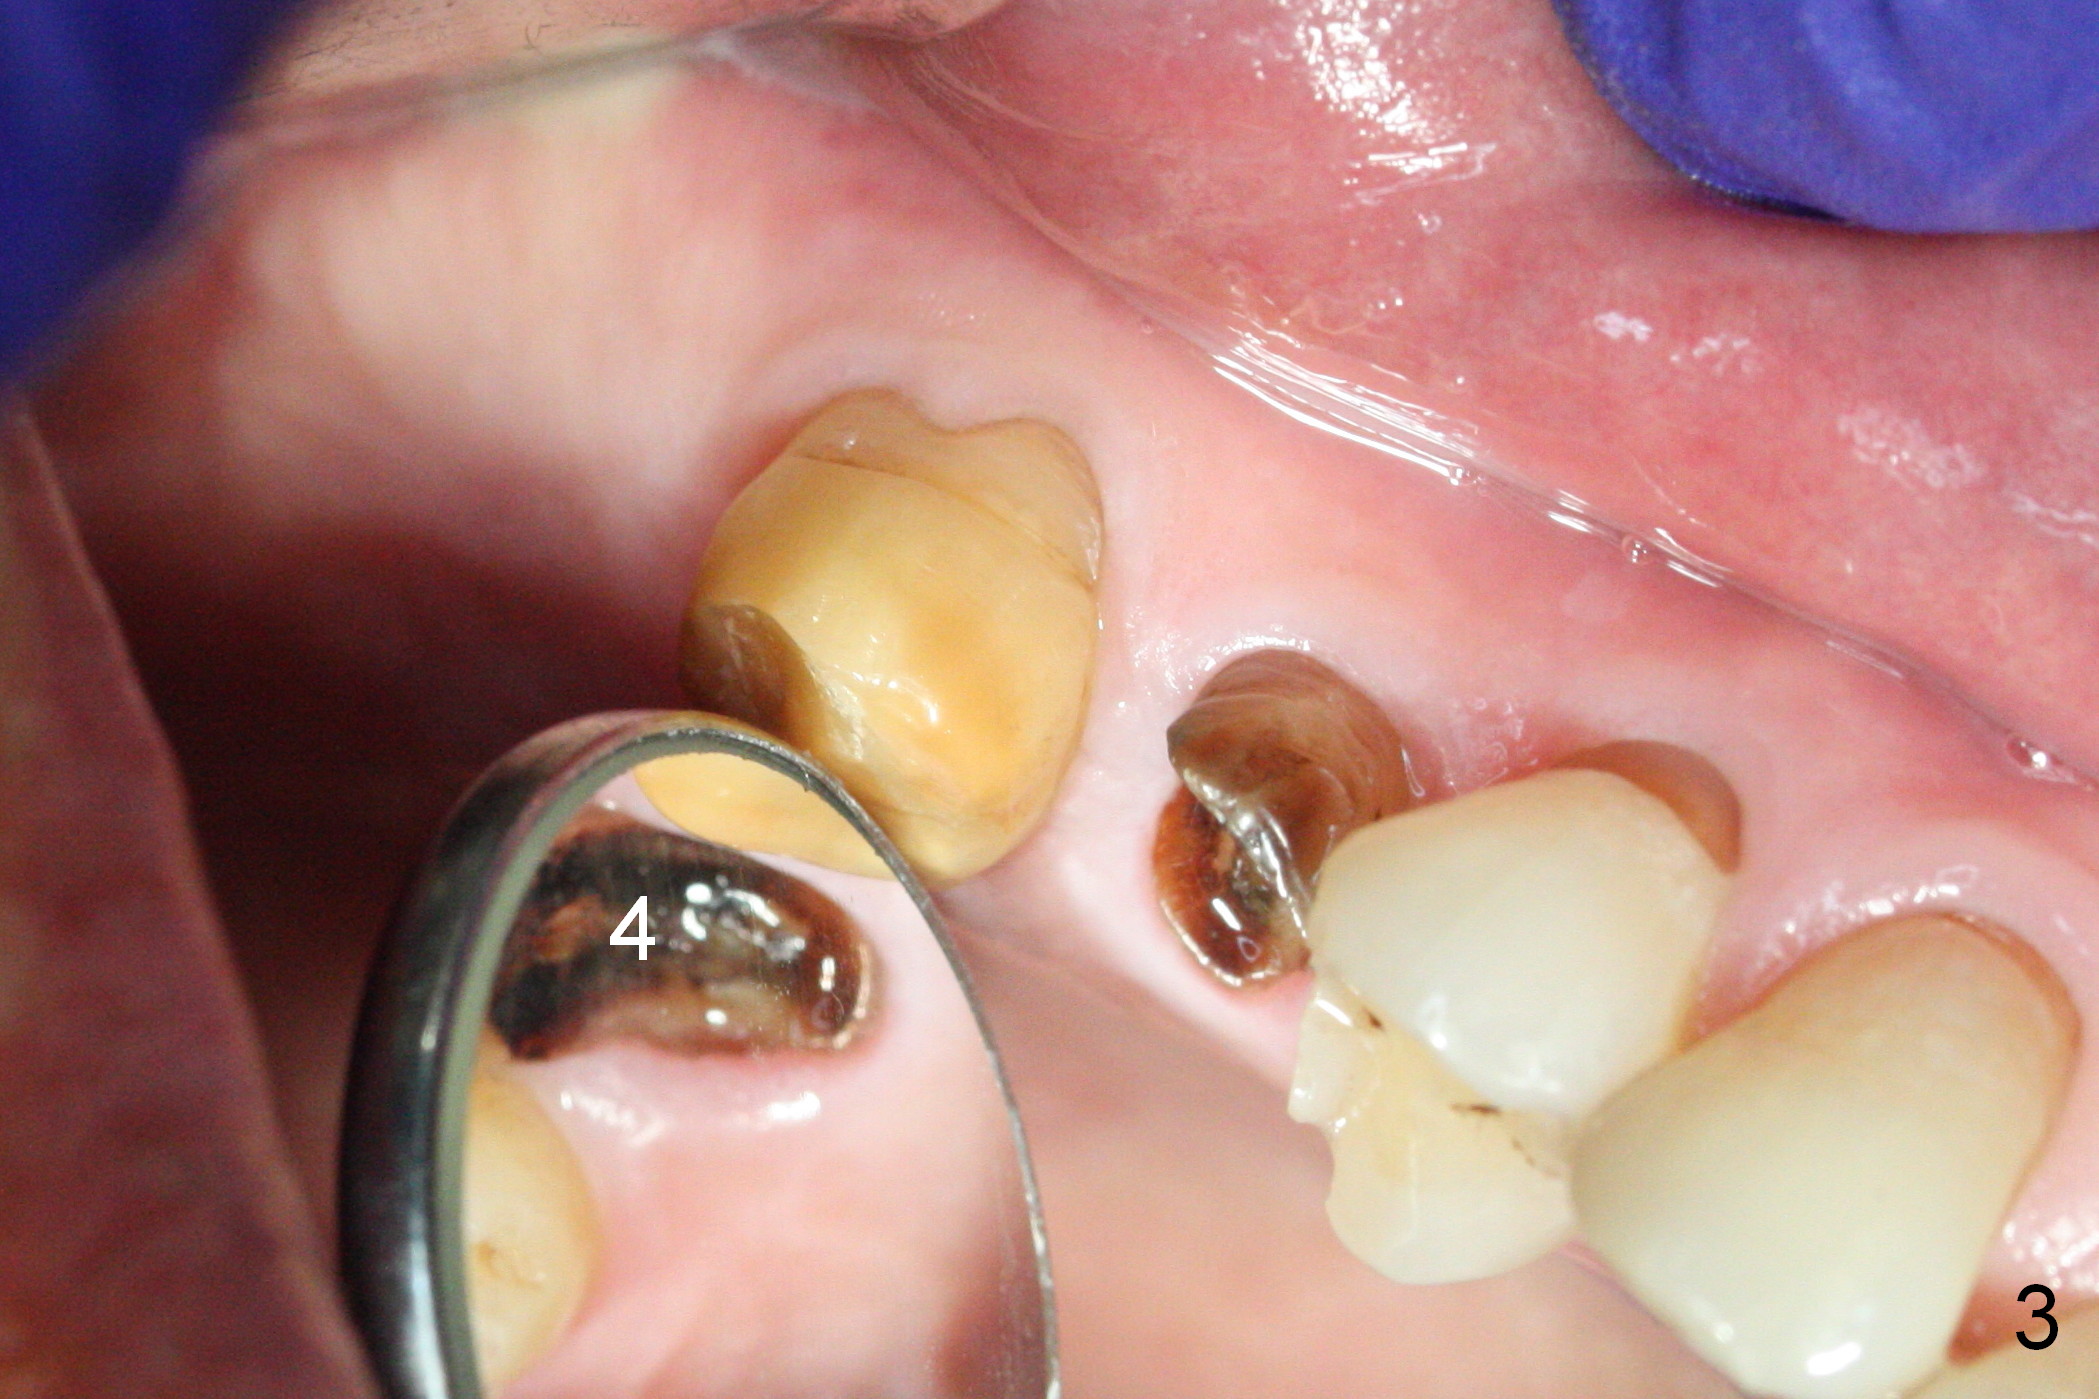

Preop exam shows posterior occlusal collapse (Fig.1) with #3 lost crown and #4 residual root. There is no ridge atrophy at #2 buccopalatally (Fig.2). The root stump of the tooth #4 is oblong, apparently consisting of 2 roots (Fig.3). There is a pointed septum at #4 socket (Fig.4, severe palatal wear of the anterior teeth (^)). After the septum is flattened with surgical handpiece and #8 round bur, 1.6 mm drill is used to start osteotomy in the septum, followed by Magic Drills (MD) and Magic Expanders (ME) alternatively. Osteotomy at #2 is initiated with Magic split, followed by MD and ME in the same manner. Dummy implants are tried in (Fig.5). Because of limited vertical height, Magicore (5.5x9(1) mm) is placed at #2, while a 4x13 mm FC implant 1-2 mm deeper than usual at #4 (Fig.6, ~ 55 Ncm). When a 5x4(2) mm pair abutment is placed at #4, there is no clearance between the Magicore at #2 and the abutment and the opposing dentition. A splinted provisional is fabricated at #3 and 4 to increase the posterior vertical height (Fig.7 P,8). In fact the occlusal contact is confined to the portion of the provisional at #3. The provisional has to extend to #4 to keep bone graft (Fig.6 *) and collagen plug in place. Liquid food is recommended at least 2-3 weeks, since there is no functional occlusal contact on the left. When the wound heals at #4 approximately 2-3 weeks, the splinted provisional can be sectioned with removal the portion at #4 to reduce micro-movement. By the evening the patient is doing well without nasal hemorrhage (sinus lift at #2 (Fig.6 *) or TMJ disturbance (due to increased vertical height).